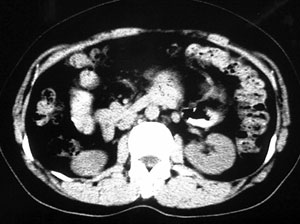

这个要问下病史,如无胰腺炎病史首先考虑胰腺体尾部的粘液囊腺瘤,此瘤太大,有分叶和实性成份要考虑恶性或潜在恶性可能,后两幅主动脉左旁结节状强化影止于左肾静脉,考虑双下腔静脉,请结合往下的片

以下是引用守望可可西里在2006-8-30 10:57:00的发言:[br][br] 定位:胰腺体尾部。[br] 定性:胰腺囊腺癌可能性大。[br] 理由:胰腺体尾部呈多囊状分叶,部分病灶与前腹壁粘连,且下部形态不规则,毛糙不整、凸凹不平。囊壁厚薄不一致,多个大小不等壁结节突入,囊壁及壁结节明显不均匀强化。偏右侧囊内见液-液平面样相对高密度,呈与壁结节类似强化。性质:1.出血?2.壁结节?